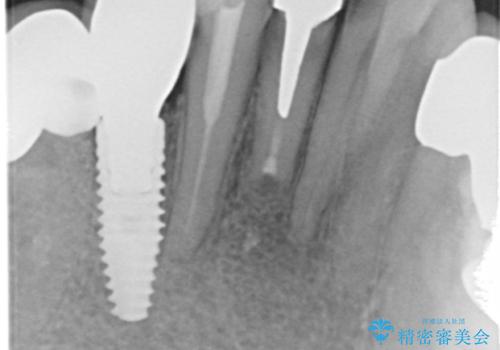

X線写真および歯周組織検査より、歯の破折 周囲骨の高度な吸収が認められました。

抜歯後、インプラントによる審美・機能改善を希望されたのでインプラント埋入に先立ち吸収した骨の再生を計画します。

歯を失う原因が虫歯や根尖病変などはなく、歯周病や歯の破折等周囲の骨を吸収する原因の場合はインプラント治療を行うに先立ち骨の造成が必要なことがあります。